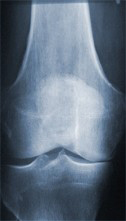

Röntgenaufnahme eines gesunden Kniegelenkes

Der Gelenkspalt entspricht einem gesunden Knie ohne Abnutzungserscheinungen des Gelenkknorpels.